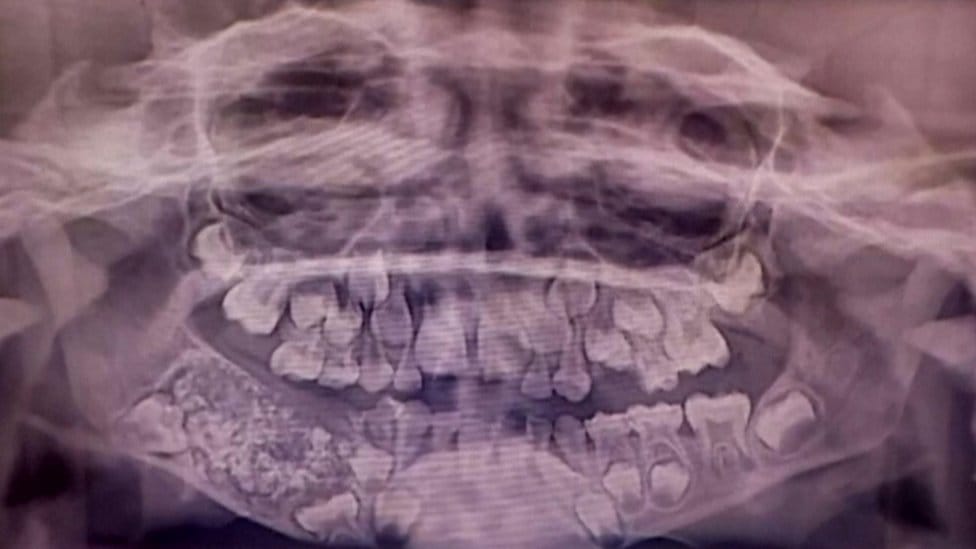

Un caso médico sin precedentes sorprendió a la comunidad científica en 2019, cuando cirujanos del Hospital de la Universidad de Saveetha, en Chennai, India, extrajeron 526 dientes de la mandíbula de un niño de siete años. El menor, que sufría desde los tres años fuertes dolores e hinchazón en el rostro, padecía un extraño odontoma compuesto, un tumor benigno relacionado con el desarrollo dental.

A los siete años, los especialistas decidieron intervenir quirúrgicamente. Tras una hora y media en el quirófano, los médicos extrajeron una masa de 200 gramos que contenía cientos de dientes rudimentarios, clasificados posteriormente en el laboratorio durante cinco horas de trabajo.

Los dientes extraídos variaban en tamaño, desde apenas 0,1 milímetros hasta 15 milímetros de longitud. La Dra. Pratibha Ramani, directora del Departamento de Patología Oral y Maxilofacial, explicó que incluso las piezas más pequeñas tenían la estructura completa de un diente normal: corona, raíz y esmalte.

El jefe del equipo quirúrgico, Dr. Senthilnathan, destacó que el tumor había bloqueado el crecimiento de los molares permanentes, pero la extracción fue exitosa y permitió conservar 21 dientes funcionales, correspondientes a la edad del paciente.

Este caso superó con creces el récord anterior documentado en Mumbai, donde se habían retirado 232 dientes a un adolescente. Con 526 piezas dentales, el niño de Chennai estableció un nuevo registro en la literatura médica mundial.